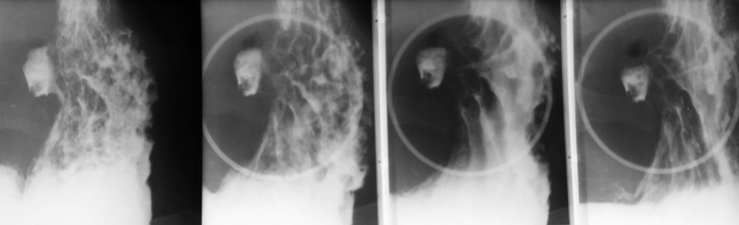

Neoplasm esofagian malign vegetant

Neoplasm faringo-esofagian malign

Neoplasm esofagian malign